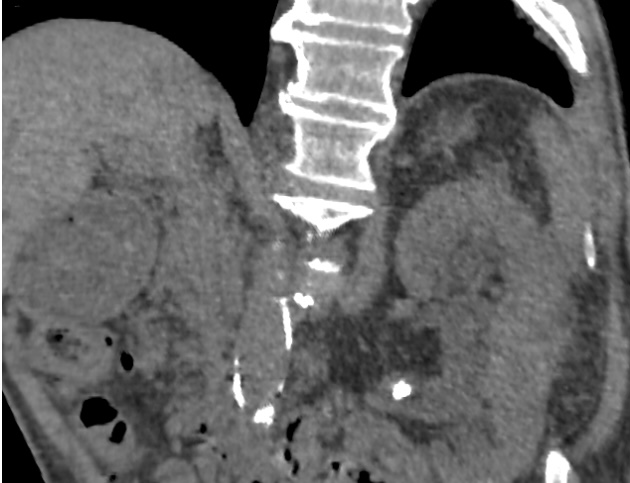

Caso 31

Diagnóstico diferencial